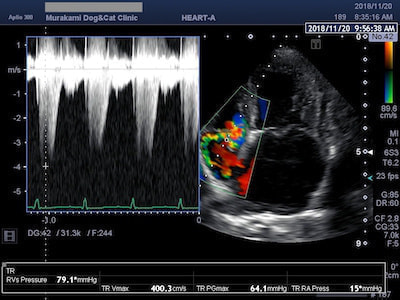

僧帽弁閉鎖不全症

高齢の小型犬に最も多くみられる心臓病が僧帽弁閉鎖不全症です。加齢による僧帽弁の変性により、弁が正常に閉じなくなり血液の逆流が生じます。進行すると逆流した血液が左心房に貯留し、左心房拡大に伴う気管支の圧迫、肺静脈のうっ血を招き、発咳や肺水腫を引き起こし呼吸困難に陥ります。治療は投薬による内科治療と、僧帽弁形成術に代表される外科治療に大別されますが、各々の病期に合わせた適切な治療が必要となります。